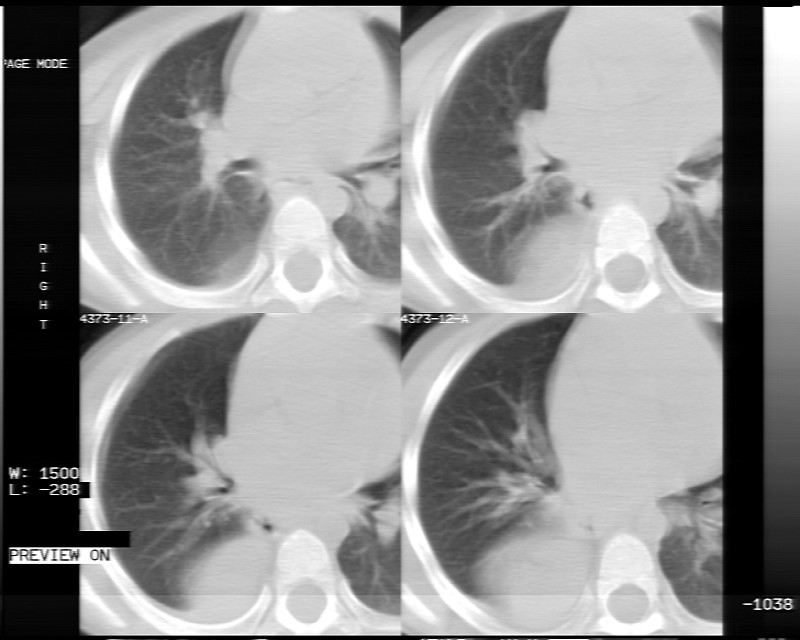

男性,3岁,斜疝术前常规检查胸片体检发现右下肺病变。咳嗽,无发烧。

象腹腔的东西,考虑膈疝

膈疝的表现

建议mpr三维重建图像,冠状位看看。

内有气体,液平面,考虑食管裂孔疝可能性大。建议食道钡透。

有液气平面,前部肺纹理聚集(受压改变),周围肺野及相邻胸膜清晰,支持膈疝,可吞服造影剂看一下。

考虑膈疝(右侧胸腹膜裂孔疝?)。